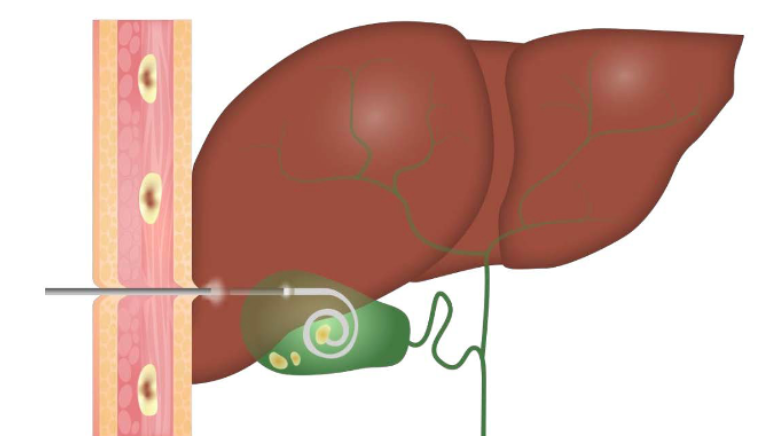

Treatment: Pyogenic liver abscess — Drainage

• Percutaneous catheter drainage: Preferred primary therapy

• Success rate: 69–90%

• Can be performed at time of diagnosis

• Catheter left in place 5–14 days until drainage resolves

• Recent success rates with antibiotics: 80–95% (even for >10 cm abscesses)

• Surgical drainage if: percutaneous fails, concurrent surgical disease, multiple/loculated abscesses